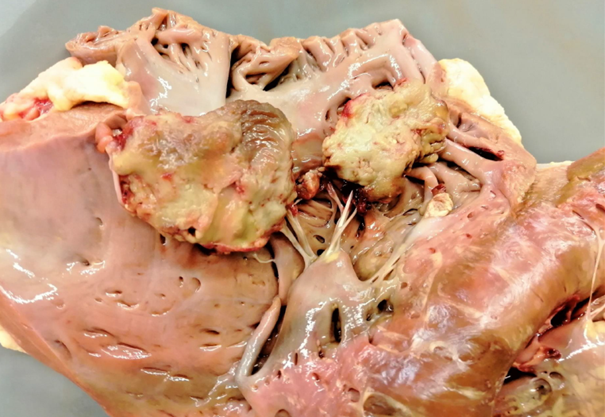

Rind, Herz/Trikuspidalklappe: Hochgradige, chronisch-aktive, multifokale, fibrinös-eitrige Endocarditis valvularis

Beschreibung:

auf der Trikuspidalklappe lassen sich multiple, blumenkohlartige Verdickungen, sowie Aufrauungen und Ulzerationen

des Klappenendothels darstellen.

Es sind dunkelrot-gelbe, unregelmäßig geformte

Fibrinauflagerungen auf und zwischen den Verdickungen zu erkennen

Hintergrundwissen/ Infektionsweg/ Pathogenese

prinzipiell bei allen Tieren, am häufigsten betroffen sind Rind (Trikuspidalis) und Schwein (Mitralis), selten bei Hund (Mitralis) und Pferd (Aortenklappe)

selten vollständige Regeneration, durch Strömung und mechanische Kräfte eher sich selbst erhaltender Entzündungsprozess, intraläsionale Bakterien sind nicht immer nachweisbar

Infektionswege/Pathogenese:

genauer Mechanismus bislang nicht vollständig geklärt (evtl. Vorschädigung durch Traumata, Sepsis, Arbeitsüberlastung)

Folge einer bakteriämischen Infektion, Endothelschäden (z.B. bakteriell-toxisch) und Thrombusbildung (i.S. Virchow-Trias)

Anhaftung an den Klappen i.F. von begünstigenden Strömungsverhältnissen und spezifischer Bakterien-Endothel-Wechselwirkung (z.B. Erysipelothrix rhusiopathiae)

Vegetativer (d.h. veränderlicher) Entzündungscharakter, fibrinös-eitrige Charakteristika gehen z.B. mit steigender Chronizität in eitrig-granulierende über

Erreger (exemplarisch):

Trueperella pyogenes (Rd.), E. rhusiopathiae (Schw.), Streptococcus spp., Staphylococcus spp. (Flfr. & Pfd.)

Komplikationen:

Mitralis: Thrombembolien (Niereninfarkte, embolisch-eitrige Herdnephritis, Stauungslunge); Trikuspidalis: Lungenembolie, embolisch-eitrige

Pneumonie, Aszites, Stauungsleber

DD für Herzklappenveränderungen: Endokardiose (Hd.), Klappenzysten, Klappenamyloidose (Rd.)